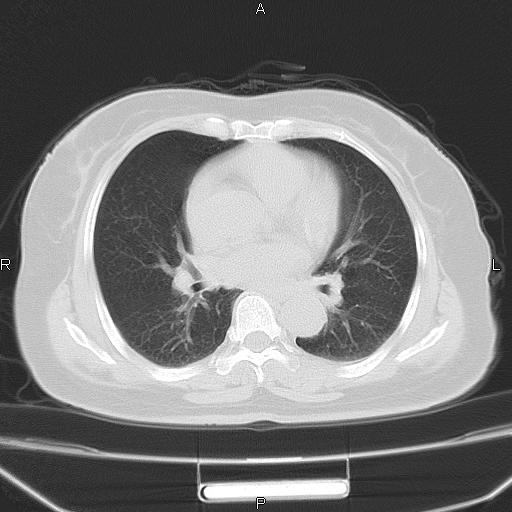

胸腺瘤

女、63Y 双眼睑下垂,早轻晚重。 胸腺瘤???

结果胸腺瘤